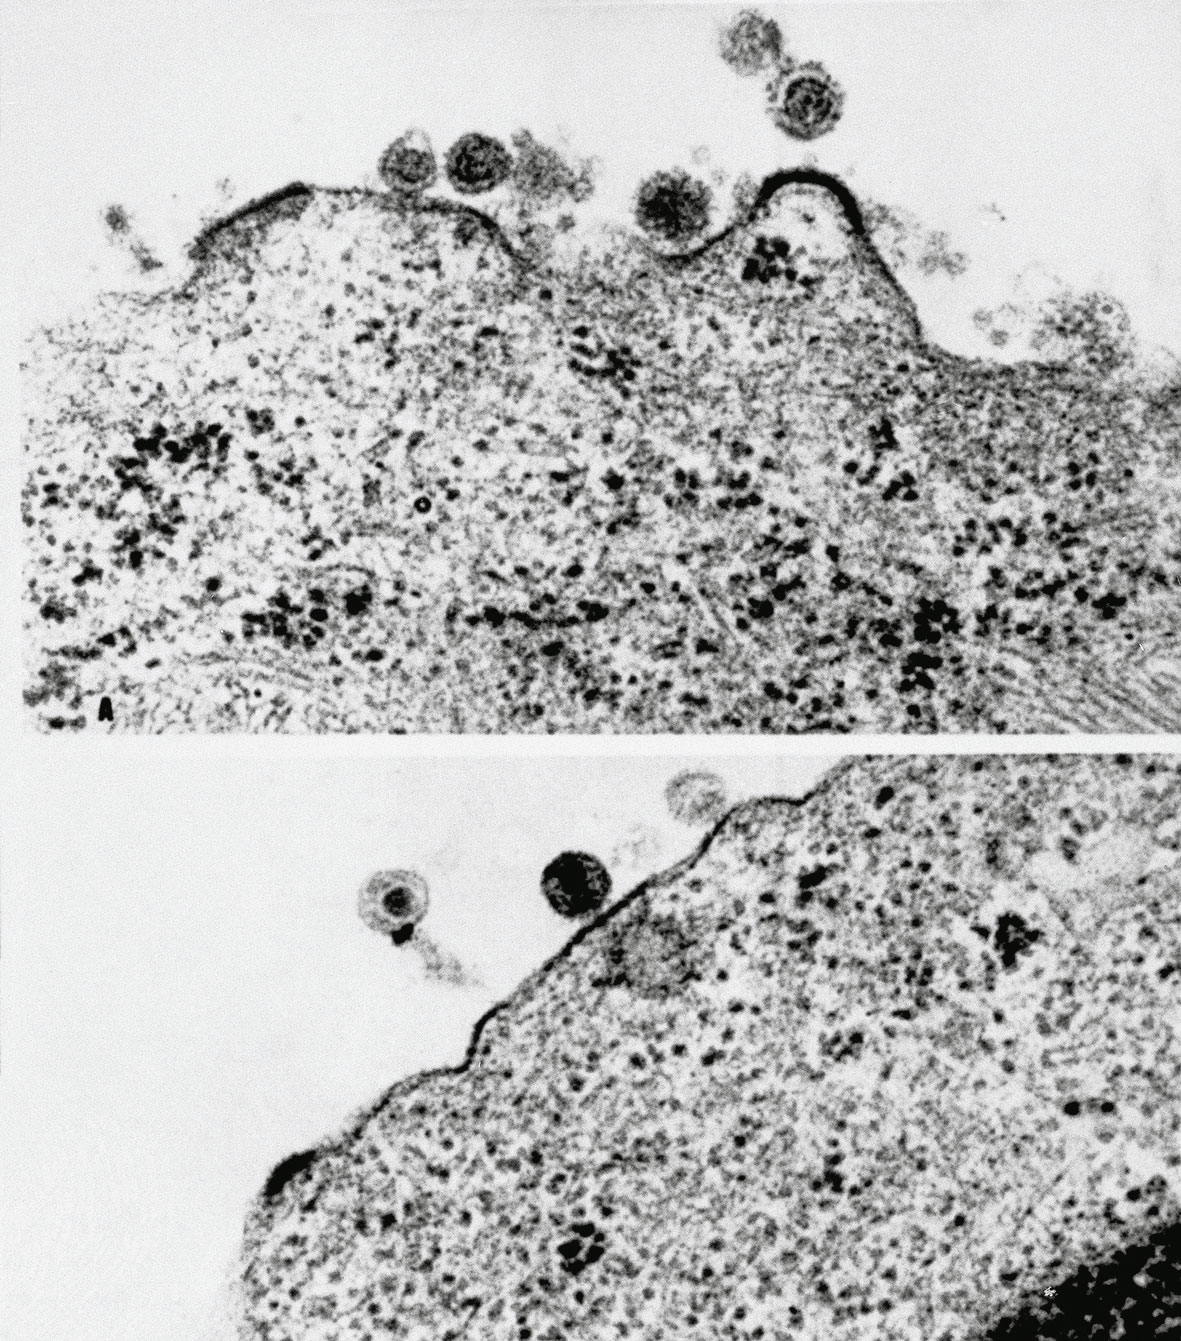

Η επιστημονική ομάδα του Παστέρ, με επικεφαλής τον καθηγητή Μοντανιέ, υποστηρίζει την ευθύνη ενός άλλου ιού, του LAV 1, που μοιάζει μορφολογικά με έναν παράγοντα που είναι υπεύθυνος για την μολυσματική αναιμία του αλόγου. Όμως οι αμερικανικές ομάδες επιστημόνων δεν μπόρεσαν να βρουν αυτό τον ιό στις περιπτώσεις που μελέτησαν.